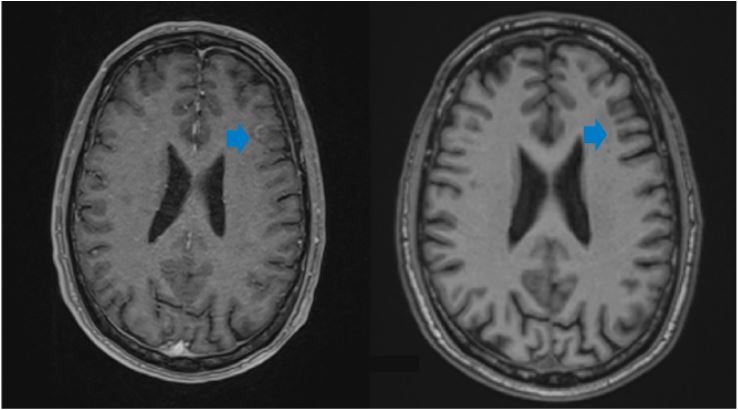

Figure 3: MRI image: Response to treatment of the left frontal lesion, baseline study October 2021 on the left and after radiotherapy and IT treatment on the right in December 2023.

In October 2022, he started treatment with pembrolizumab 200 mg every 21 days, with stabilization of the disease at the first radiological re-evaluation. To date, he has completed 15 cycles with excellent tolerability and no relevant side effects, and analgesics have been discontinued. The patient was last evaluated in December 2023 and is in systemic and cerebral response (Figure 3).